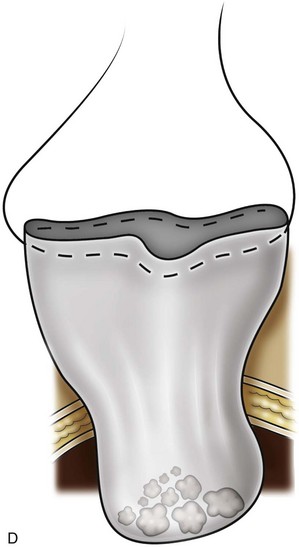

Patients with symptomatic calyceal diverticula containing stones can be managed laparoscopy. ESWL and ureteroscopy may be employed, but due to infundibular stenosis, stone clearance rates are low (Jones et al, 1991; Pang et al, 1992; Stream et al, 1992). The principles of treatment include the removal of stones and widening of the infundibular stenosis to prevent urine stasis or ablation of the diverticula cavity. In the past, symptomatic calyceal diverticula have been managed with partial nephrectomy, with marsupialization and fulgaration of the diverticulum, and occasionally simple nephrectomy. More recently, percutaneous treatment has been used, but stones or symptoms may recur if the cavity is not fully ablated (Donnellan et al, 1999). A laparoscopic approach may be indicated with large, peripheral diverticula, or for centrally located diverticula with proximity to the renal hilum.

The location of the diverticula will be the primary driver for choosing either a transperitoneal or retroperitoneal approach. Once the renal dissection is completed, locating the diverticulum may prove difficult. The presence of dense adhesions on the surface of the kidney overlying the divericulum may be present along with a “dimpling” effect on the renal capsule. Intraoperative ultrasonography may also be used to aid in the location of the divertiulum or to confirm a suspected location. Once localized, the overlying parenchyma is incised and opened to expose the diverticulum, which is subsequently opened with cautery. Stones may then be removed, and the argon beam coagulator or monopolar cautery device can be used to fulgarate the diverticular lining. The collecting system is closed with suture, and perirenal fat may be placed into the defect to further decrease the likelihood of recurrence. A drain is usually left in place.

Published reports on laparoscopic calyceal diverticulectomy are limited to small series and case reports. Excellent results have been reported by numerous authors, demonstrating the definitive nature of this treatment modality (Miller et al, 2002; Gluckman et al, 1993; Ruckle and Segura et al, 1994; Harewood et al, 1996; Wolf, 2000; Canales and Monga, 2003; Wyler et al, 2005). Probably due to the rarity of this surgery, complications are also rare and have not been reported yet in the literature.